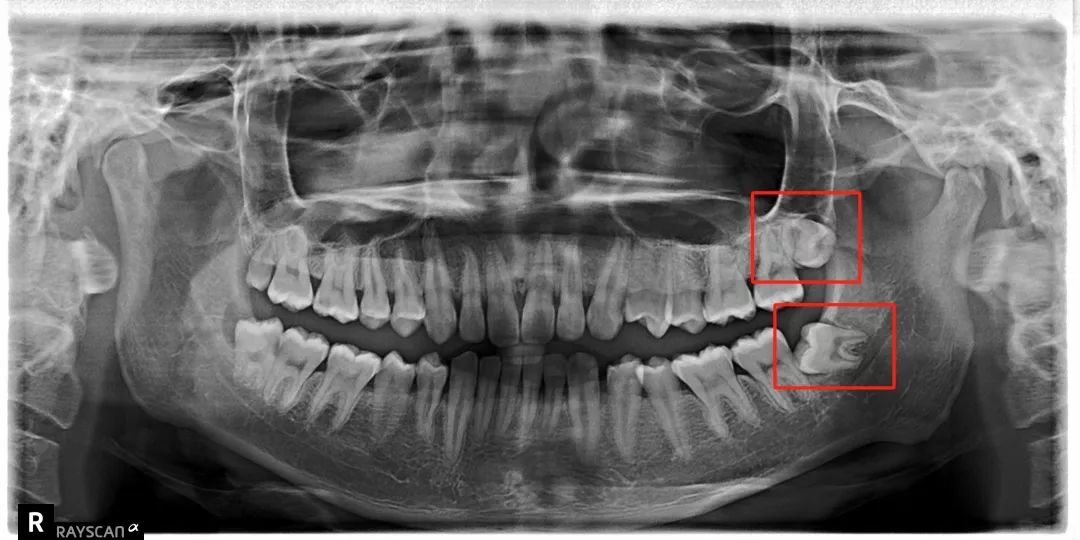

科普一波智齿~

把整副牙齿挤歪:

比方说像树根一样长出很多「根」

扎根在骨头里,死死抓住